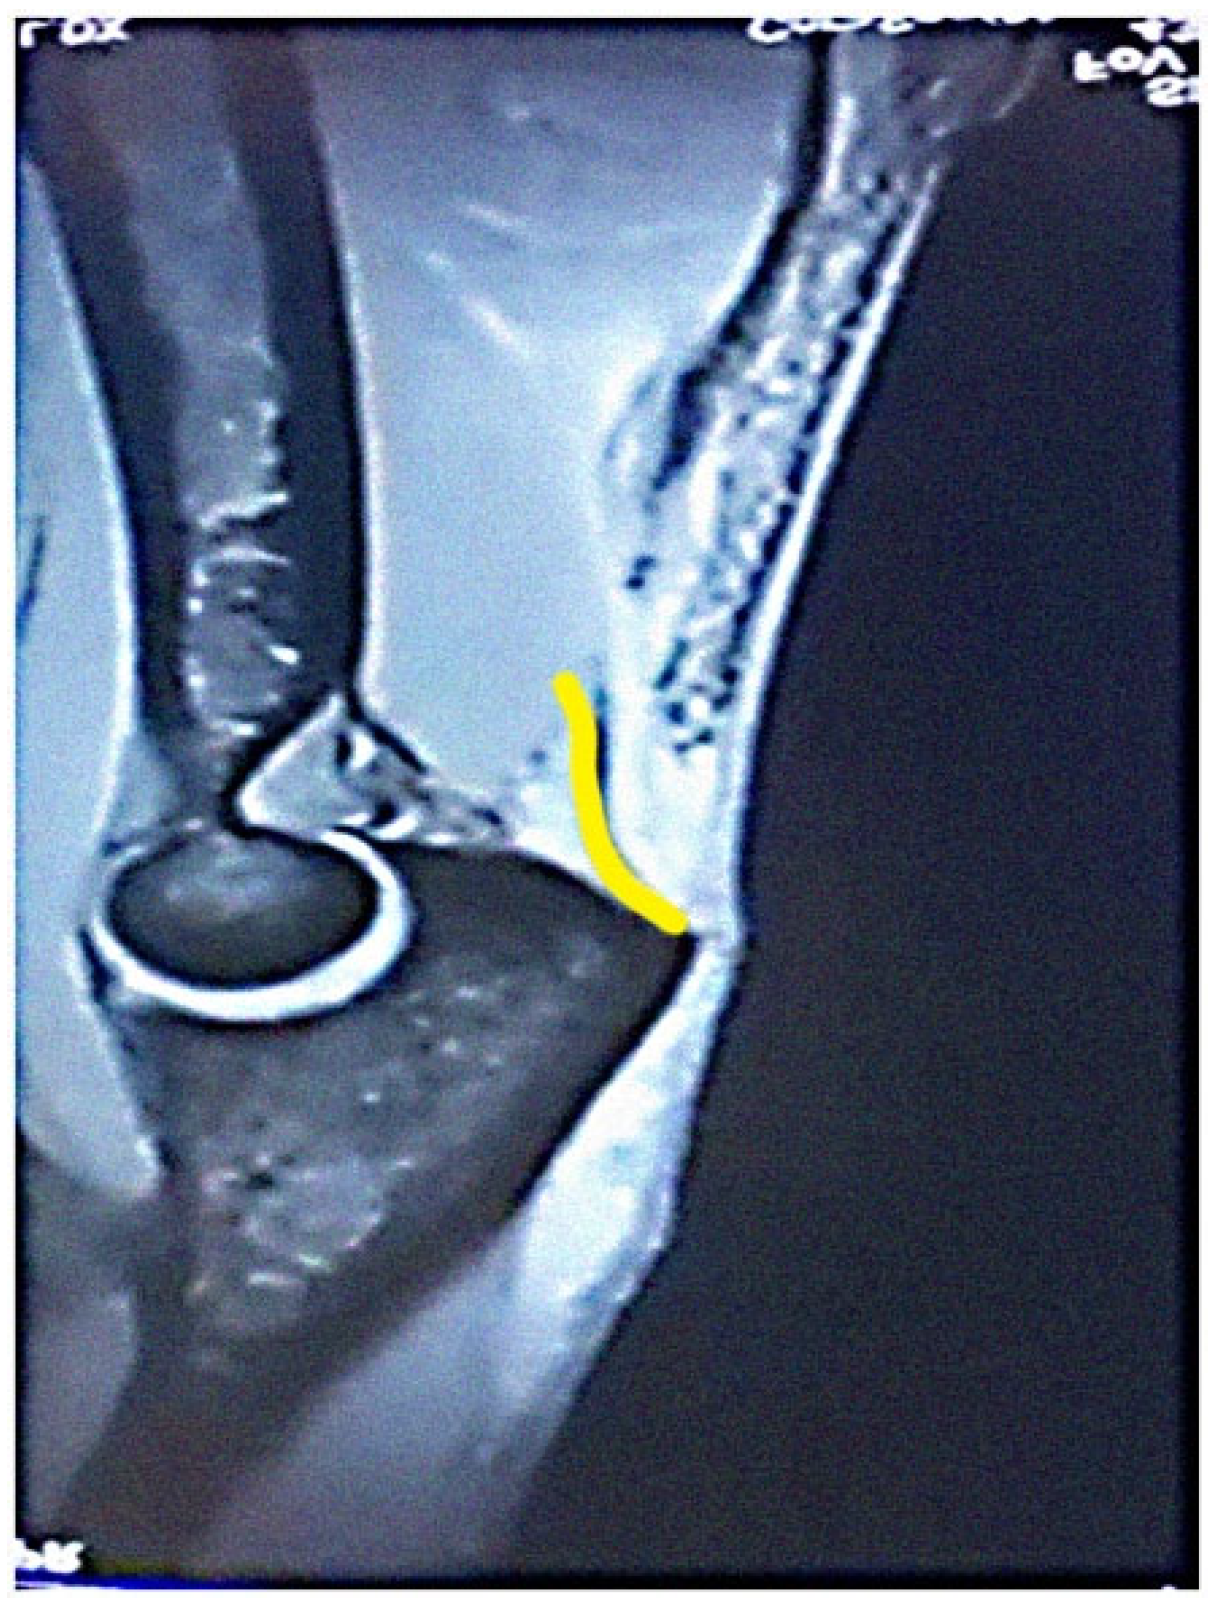

The most common tendon injuries are rotator cuff tears of the shoulder, hand flexor injuries, and achilles tendon injuries [1]. Triceps tendon rupture is the least reported among all the tendon injuries in the literature [2,3]. 65 years ago, Anzel evaluated a series of 1014 patients with tendon ruptures in various locations, and triceps tendon ruptures accounted for only 0.8% of this series [4]. Currently the prevalence is increasing, and the prevalence of triceps tendon injuries has been found to be 3.8% [5]. Theoretically, the types of tendon injuries are tendon avulsion or inside the muscle belly. In practice, a rupture almost always occurs in the area of the tendon-bone junction, and the cause is an eccentric contraction of the triceps causing a tendon deformity of more than 8% [6]. Traditionally the triceps tendon has a uniform attachment to the olecranon ulnae. This premise has caused problems in assessing the degree of damage in traumatic triceps tendon ruptures. In 2006, an anatomic study by Madsen confirmed that in most cases the medial head of the triceps has a single attachment to the olecranon ulnae [7]. This insertion is located in a deeper layer and forms a narrower part of the attachment, and very rarely is only this part damaged [8]. The long and lateral head of the triceps has a common attachment that runs more superficially, gradually extending laterally into the surrounding area towards the musculus anconeus, which helps to strengthen the bone-tendon junction. The width of the attachment correlates with the size of the olecranon and ranges from 20 to 40 mm. Paradoxically, the thickness of the tendon is not as pronounced. The attachment itself occupies a large surface area, reaching 400 mm2 in diameter and is dome-shaped [9]. These current findings are particularly important in partial tendon ruptures when a decision has to be made whether to proceed conservatively or with surgical revision. MRI is an appropriate method of choice to accurately assess the current condition. A schematic representation of the three basic types of partial DTTR rupture can be seen in Figure 1, while the normal anatomic attachment relationships of the triceps tendon in sagittal section to the olecranon ulna and a sub-complete rupture of the triceps tendon of the right hand are shown in Figure 2 and Figure 3. Furthermore, the place of attachment of the individual heads of the triceps to the olecranon ulnae is presented in Figure 4.

Figure 2. Normal anatomic attachment relationships of the triceps tendon in sagittal section to the olecranon ulnae. MRI: A—olecranon, B—medial head, C—common tendon of lateral and long head (own source).